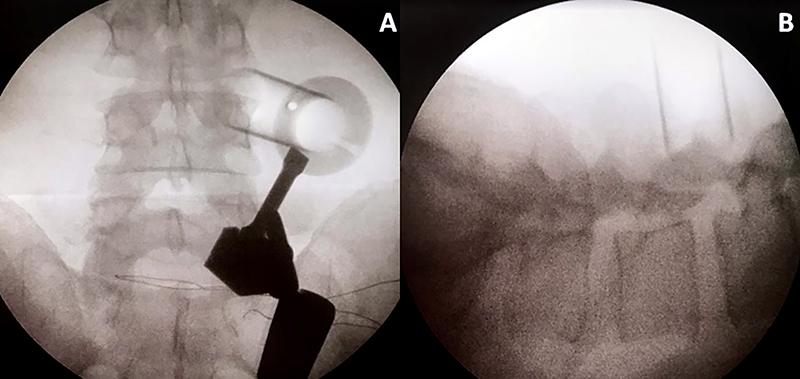

Paciente masculino, de 54 años de edad con dolor crural derecha y parestesias en igual región de tres semanas de evolución con escasa respuesta al tratamiento médico. Al examen físico, presentó paresia del cuádriceps derecho e hipoestesia en cara anterior del muslo y dolor según EVA=9. En RM se observa protrusión discal extraforaminal derecha en nivel L3-L4 (fig. 2). Se propuso una discectomía mínimamente invasiva mediante sistema tubular y microscopio. Se observó una mejoría en 8 puntos en la EVA (Video 1).

Figura 2: RM sagital y axial del caso ilustrativo.